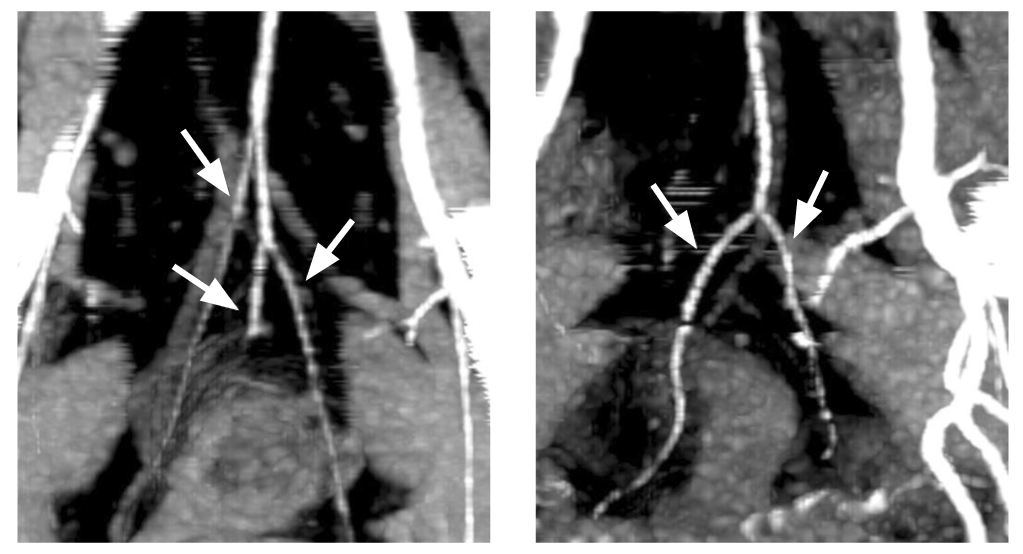

In all cases where interpretation was possible, six terminal branches of the superior rectal artery were identified, localized at 1, 3, 5, 7, 9, and 11 o’clock positions on the conventional dial (Fig. 2). Several anatomical variants of the upper rectal artery branching and its path to the rectal wall were revealed (Fig. 3 and Table 1). The superior rectal artery branches into three, with each branch subsequently splitting. This classical variant accounts for 54% of cases, as shown in Figure 3 (depicting the first, fifth, and sixth variants). Figures 4 and 5 are also included.

In 34% of cases, two branches of the upper rectal artery were identified, leading to trifurcation. The posterior branches branched off in the form of arcs to the posterior wall of the intestine at 5 and 7 o’clock of the conventional dial (variant 2). Figure 6 displays the first and second variants. In two observations, a vascular arcade in the form of an arc was found, which fed almost the entire circumference of the intestine, according to the blood supply type of the small intestine (variant 3) (Fig. 7). In six cases, variant 4 (Fig. 8) showed the scattered type, with six separate branches from the superior rectal artery to the intestinal wall, either simultaneously or consecutively. In 4% of cases, variant 7 had four branches of the upper rectal artery, two of which split and two went separately.

Fig. 6. Trifurcation of the superior rectal artery on the left and bifurcation of the superior rectal artery on the right (arrows). Computed tomography reconstruction.